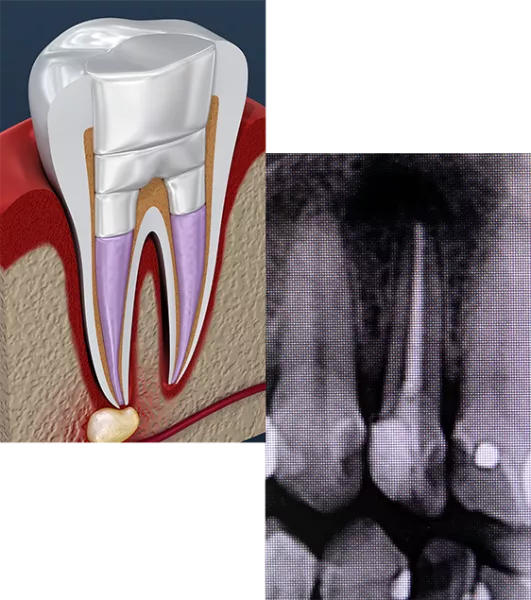

Endodnotics is commonly known as a root canal. It involves the removal of the pulp of the tooth.

If you’re experiencing a severely infected tooth, often the best course of action is a root canal. A root canal is a treatment designed to repair and save a badly damaged or infected tooth rather than removing it.

By removing the infected inner tissue—the pulp—of the tooth with a root canal, we both treat the current infection and help prevent a future infection. Since an infection can spread to other tissues surrounding the infected tooth, immediate action is important.

The root canal process begins by drilling a small hole in the tooth, through which the dentist removes the inner pulp. The dentist then seals this hole, or may choose to restore the tooth with a dental crown. Since we give every patient a local anesthetic before treatment—just like with fillings—patients typically don’t feel a thing.